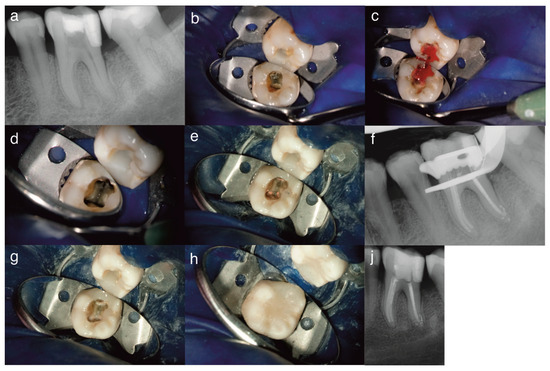

Objective: To report a rare case of pulp space tissue growth in a mature mandibular molar with severe endo-periodontal involvement after conservative endodontic treatment and to discuss the possible biological explanations, including regeneration and granulation tissue healing. Severe endo-periodontal lesions are challenging, particularly [...] Read more.

Objective: To report a rare case of pulp space tissue growth in a mature mandibular molar with severe endo-periodontal involvement after conservative endodontic treatment and to discuss the possible biological explanations, including regeneration and granulation tissue healing. Severe endo-periodontal lesions are challenging, particularly as endodontic regeneration is usually observed in immature teeth, while revascularization in mature teeth, especially in cases of advanced periodontal disease, is rare, as demonstrated in this case. Methods: This study reports a rare case of tissue regeneration versus granulation tissue healing in the pulp space, occurring alongside periodontal healing, in a mature mandibular molar with necrotic pulp and severe periodontal involvement. A 52-year-old patient presented with a mature mandibular molar (tooth #19) exhibiting necrotic pulp with severe endo-periodontal involvement, including grade-3 mobility, tenderness to percussion, a 12 mm probing depth, and extensive periradicular radiolucency. The tooth was diagnosed with necrotic pulp and symptomatic apical periodontitis and was deemed hopeless, with extraction planned. Results: Following patient refusal, endodontic treatment was initiated, including cleaning, shaping, and placement of the intracanal medicament, Ledermix. The patient canceled the extraction due to symptom resolution and disappeared for 12 months. On return, the patient presented with spontaneous pain exacerbated by thermal stimuli, consistent with symptoms of irreversible pulpitis. Clinical examination revealed significant clinical and radiographic improvements, including reduced probing depth (3 mm), no mobility, resolution of apical translucency, radiographic findings suggestive of canal narrowing, and a positive pulp sensibility response. Re-entry elicited profuse bleeding with newly formed vital tissue beneath the medicament. Sodium hypochlorite irrigation failed to achieve hemostasis; inflamed tissue was removed; root canals were cleaned, shaped and obturated; and treatment was completed with placement of a permanent coronal resin composite restoration. A forty-month follow-up showed an asymptomatic tooth with clinical and radiographic healing. Conclusions: This case demonstrates that conservative endodontic management may result in favorable clinical and radiographic outcomes in mature teeth with severe endo-peroidontal involvement, influencing extraction decisions. It provides clinical evidence suggestive of tissue regeneration and periodontal healing in a mature tooth with necrotic pulp and severe periodontal compromise, challenging conventional prognosis. The observed pulp space tissue growth may be suggestive of regeneration; however, alternative explanations, including granulation tissue healing or repair processes, cannot be excluded. Healing by granulation tissue in the pulp space remains possible. Root canal treatment in advanced endo-perio lesions can yield favorable outcomes and may influence extraction decisions. Further clinical and histological studies are needed to clarify underlying mechanisms and optimize treatment strategies. Full article

Show Figures

Figure 1